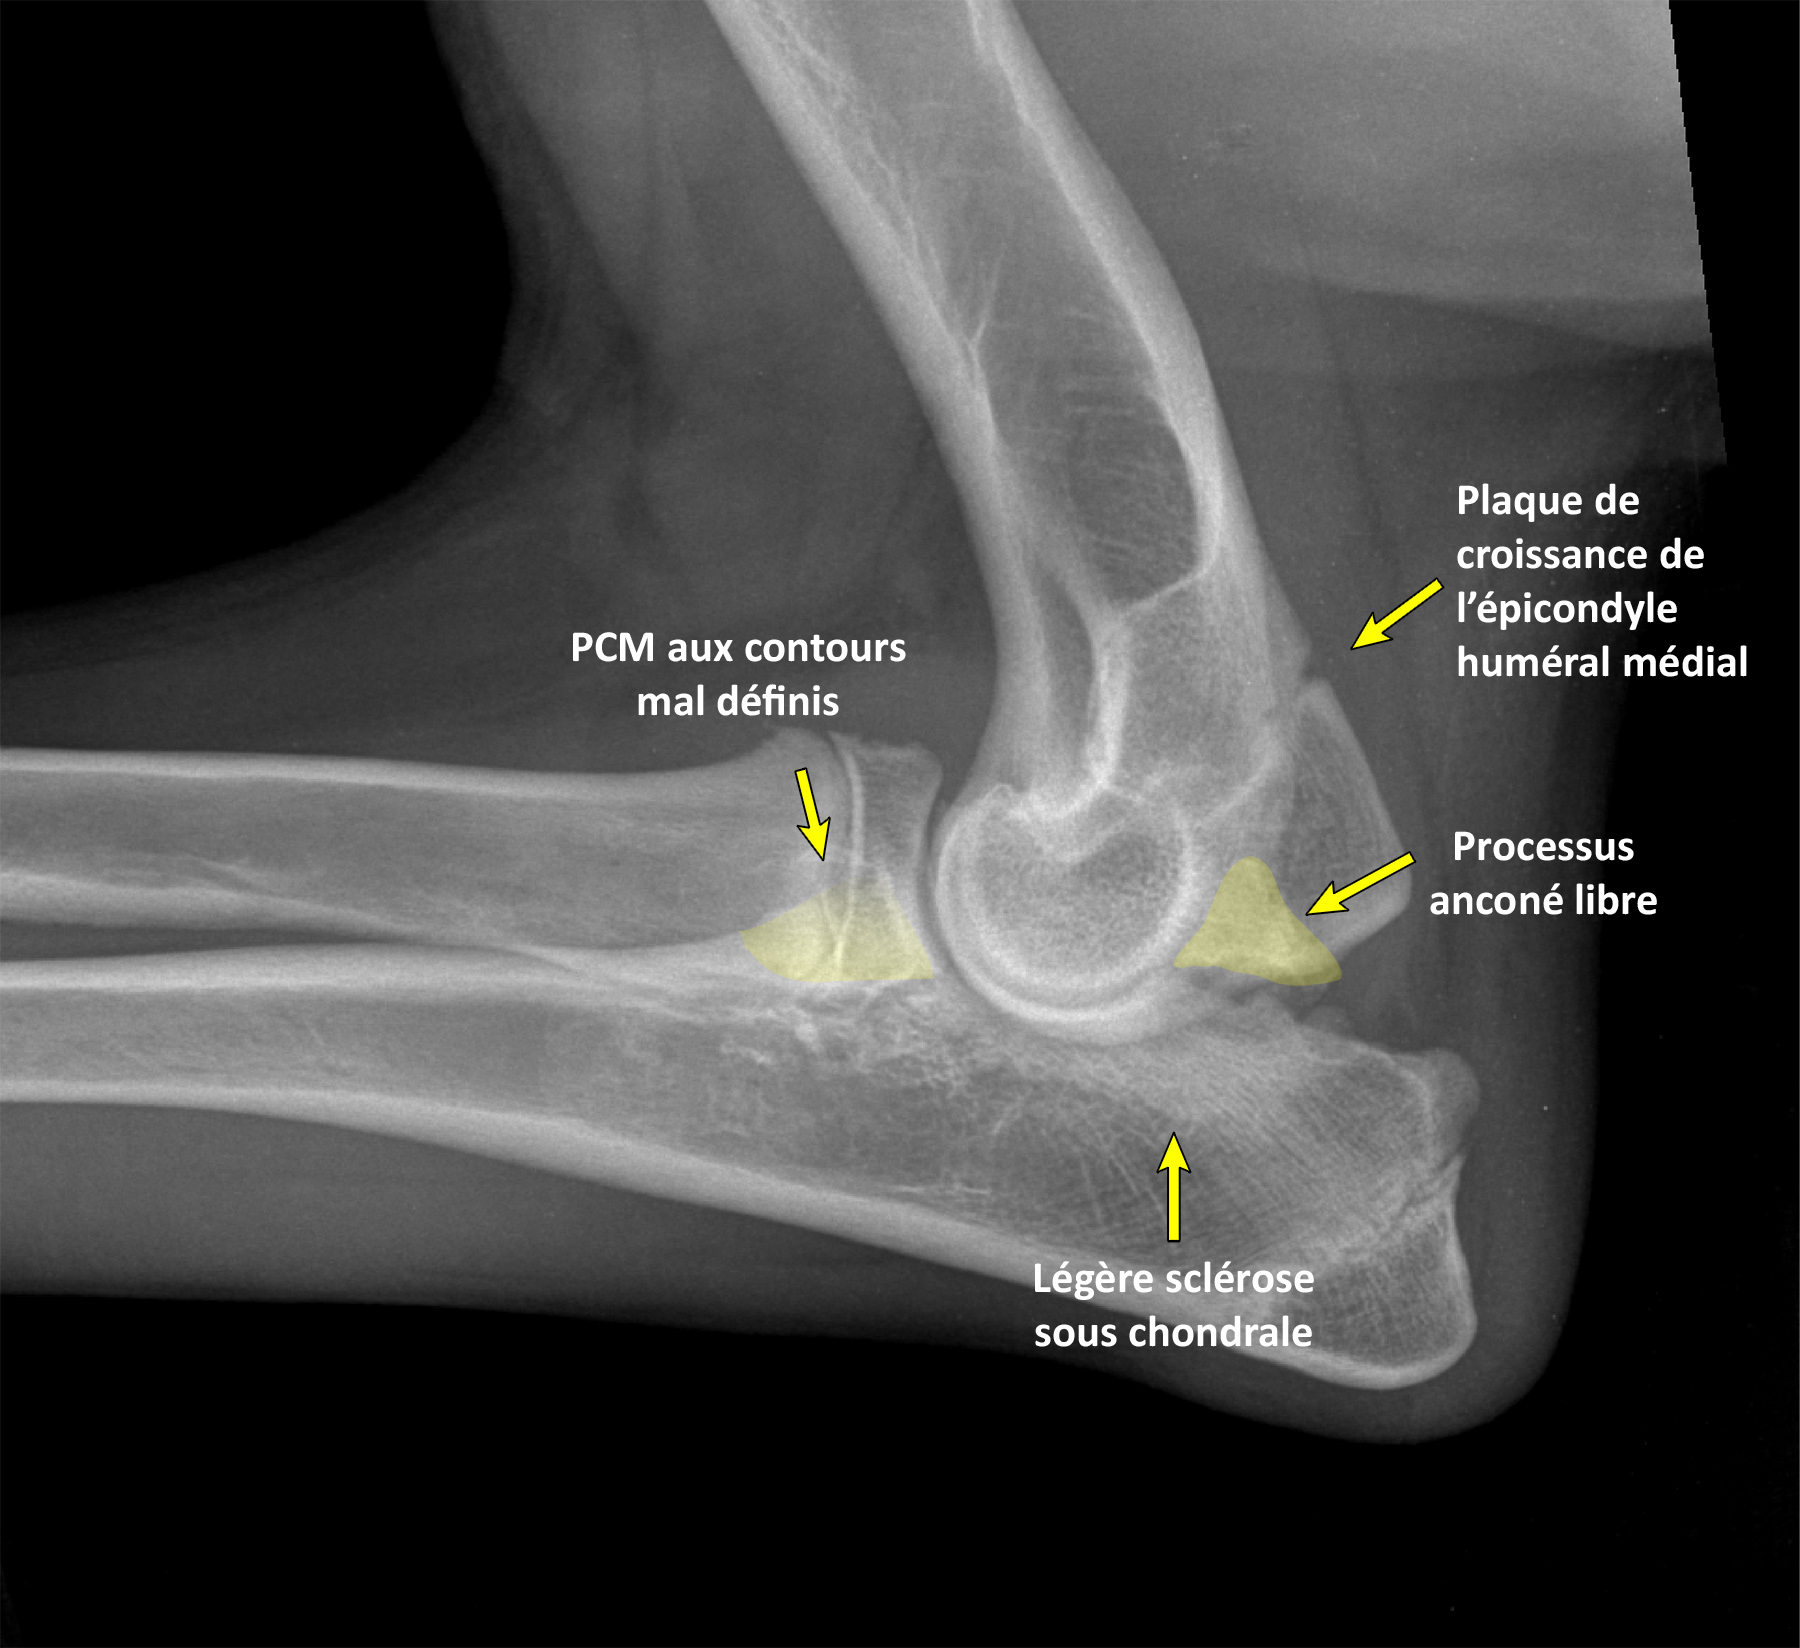

laterale-annotee